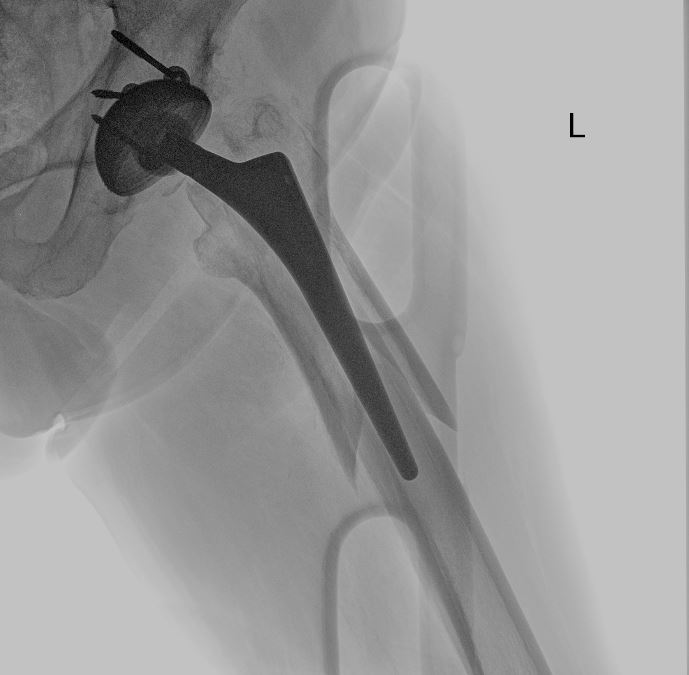

uomo di 64 anni portatore di due protesi ad entrambe le anche eseguite nel 2013 e nel 2015, mentre va in bicicletta in una strada di medio traffico viene tamponato da un furgone e riporta la frattura periprotesica diafisaria prossimale del femore sinistro (protesi eseguita nel 2015).

Il giorno 16 dicembre 2019 viene eseguito intervento chirurgico di Revisione, osteosintesi con placca ad uncino e sostituzione stelo, periodo post operatorio trascorso in maniera ottimale.